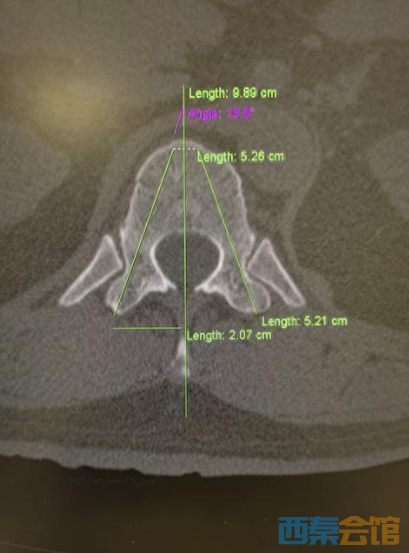

患者伤情影像

针对伤情,武汉大学泰康临床学院/泰康同济(武汉)医院创伤外科主任张俊与骨科主任姚士军迅速组建救治团队,对影像学资料进行详细研判,结合患者高血压病史,综合评估骨折稳定性及神经受压风险。经讨论,团队决定采用经皮椎弓根钉棒复位内固定术。该术式属微创范畴,可在实现骨折复位固定的同时,最大限度减少对腰背部肌肉及软组织的损伤,有利于患者术后早期功能锻炼及快速康复。

3月12日,手术按计划进行。术中,在C臂机透视引导下,主刀医生张俊主任于患者腰背部选取1.5至2厘米的微小切口,经导针准确定位椎弓根,依次置入螺钉及连接棒,并对压缩椎体进行撑开复位。术中X线检查显示,骨折复位满意,内固定物位置良好。整场手术历时近3小时,过程顺利。